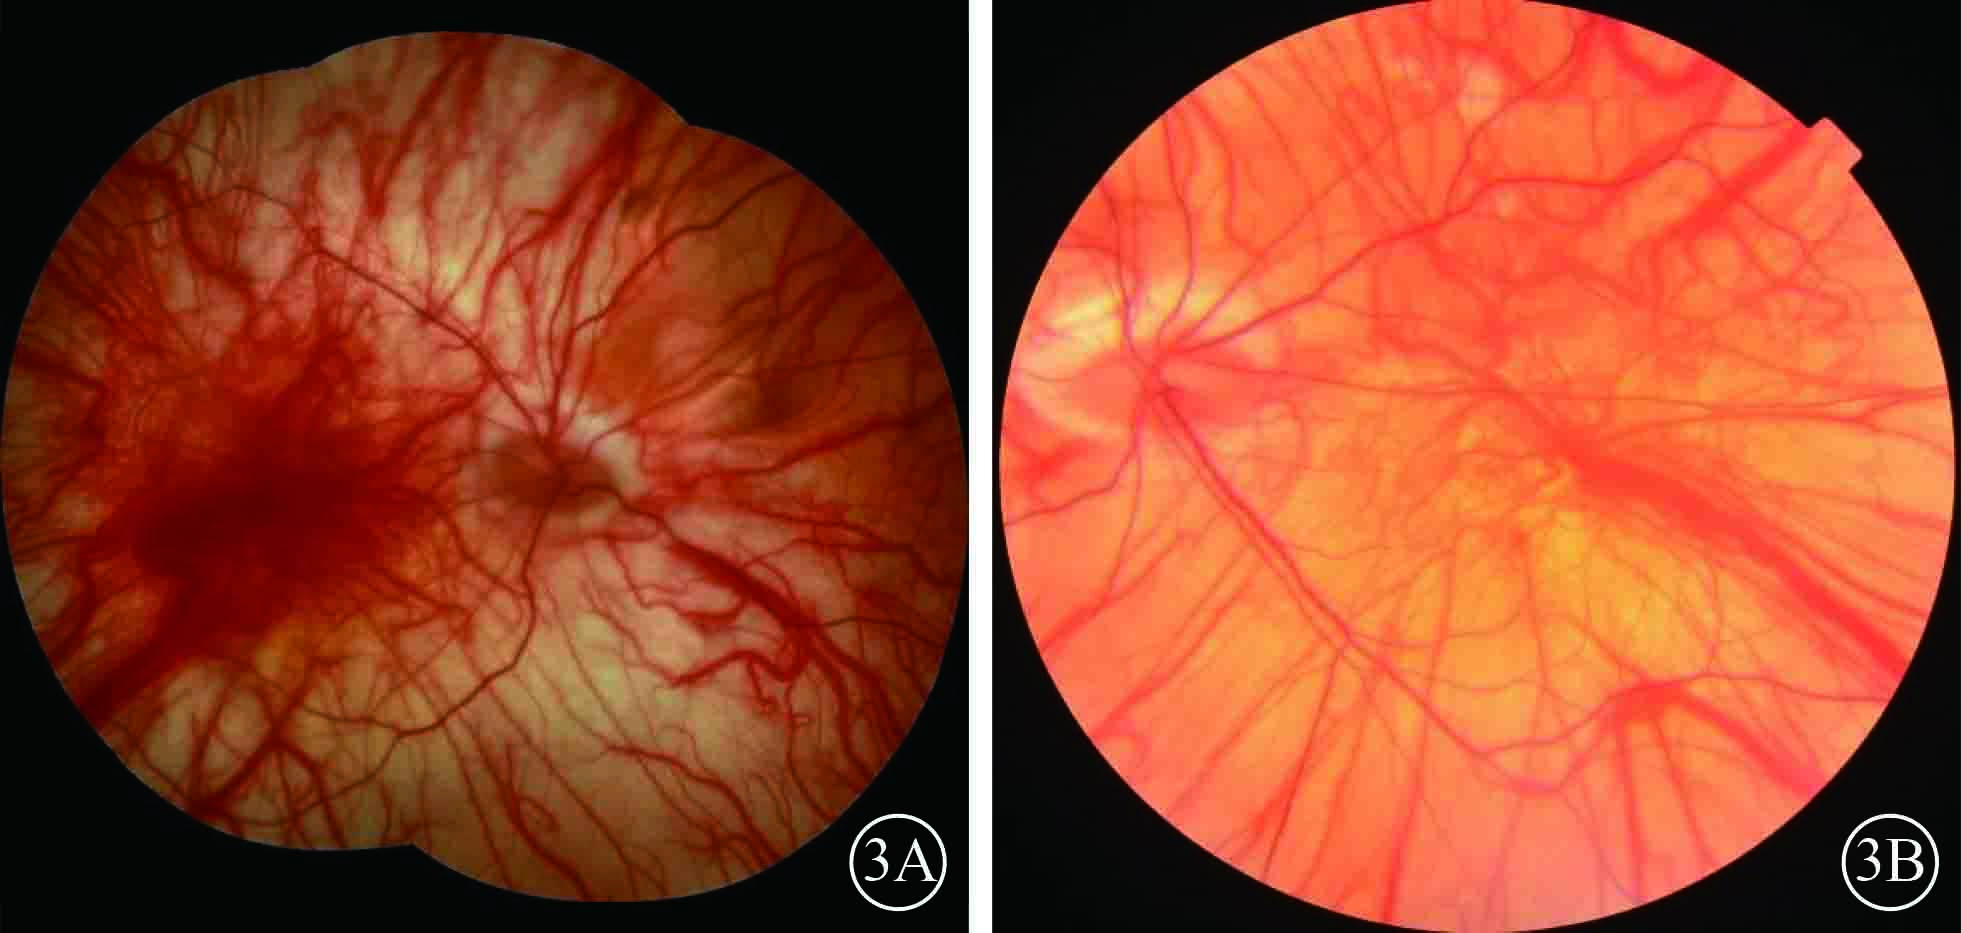

圖3

硅油取出手術后3個月雙眼彩色眼底像。3A. 右眼;3B.左眼。雙眼視網膜復位,眼底無色素,透見脈絡膜大血管

圖3

硅油取出手術后3個月雙眼彩色眼底像。3A. 右眼;3B.左眼。雙眼視網膜復位,眼底無色素,透見脈絡膜大血管

患者男,35歲。因體檢發現雙眼視網膜脫離1月余于2015年3月12日來我院眼科就診。患者自幼皮膚、毛發、虹膜無色素;雙眼視力差、畏光。否認外傷史、家族史。眼部檢查:右眼視力數指/30 cm,左眼視力0.1;雙眼矯正視力均無提高。雙眼眼瞼皮膚及睫毛均無色素;眼球水平震顫;角膜透明,瞳孔圓,虹膜半透明;晶狀體透明。雙眼眼底呈橙色。右眼全視網膜脫離,左眼0~8點時鐘位視網膜脫離(圖1);雙眼視網膜裂孔均窺不清。A型超聲檢查,右眼、左眼眼軸長度分別為26、28 mm。診斷:(1)雙眼孔源性視網膜脫離(疑似);(2)雙眼高度近視;(3)眼皮膚白化病。分別于2015年3月23日、5月11日行左眼、右眼視網膜復位手術。采用標準25G經睫狀體平坦部玻璃體切割手術。手術中見左眼視網膜裂孔分別位于 1、2、4、6點時鐘位,右眼裂孔位于8、11點時鐘位。先采用眼內電凝對裂孔邊緣進行標記,電凝處理后裂孔邊緣呈白色外觀(圖2);視網膜復位后,采用視網膜冷凍替代常規激光光凝對裂孔進行封閉;最后進行硅油眼內填充。雙眼均于手術后3個月行硅油取出手術。硅油取出后3個月,雙眼視網膜復位良好,眼底呈橙色,透見脈絡膜大血管(圖3);6個月,右眼視網膜復位良好,左眼下方視網膜再次脫離。于2016年2月1日再次行左眼視網膜復位手術、硅油填充。2016年12月27日隨訪,右眼視網膜復位良好;左眼硅油填充,下方視網膜仍有局部脫離(圖4)。

患者男,35歲。因體檢發現雙眼視網膜脫離1月余于2015年3月12日來我院眼科就診。患者自幼皮膚、毛發、虹膜無色素;雙眼視力差、畏光。否認外傷史、家族史。眼部檢查:右眼視力數指/30 cm,左眼視力0.1;雙眼矯正視力均無提高。雙眼眼瞼皮膚及睫毛均無色素;眼球水平震顫;角膜透明,瞳孔圓,虹膜半透明;晶狀體透明。雙眼眼底呈橙色。右眼全視網膜脫離,左眼0~8點時鐘位視網膜脫離(圖1);雙眼視網膜裂孔均窺不清。A型超聲檢查,右眼、左眼眼軸長度分別為26、28 mm。診斷:(1)雙眼孔源性視網膜脫離(疑似);(2)雙眼高度近視;(3)眼皮膚白化病。分別于2015年3月23日、5月11日行左眼、右眼視網膜復位手術。采用標準25G經睫狀體平坦部玻璃體切割手術。手術中見左眼視網膜裂孔分別位于 1、2、4、6點時鐘位,右眼裂孔位于8、11點時鐘位。先采用眼內電凝對裂孔邊緣進行標記,電凝處理后裂孔邊緣呈白色外觀(圖2);視網膜復位后,采用視網膜冷凍替代常規激光光凝對裂孔進行封閉;最后進行硅油眼內填充。雙眼均于手術后3個月行硅油取出手術。硅油取出后3個月,雙眼視網膜復位良好,眼底呈橙色,透見脈絡膜大血管(圖3);6個月,右眼視網膜復位良好,左眼下方視網膜再次脫離。于2016年2月1日再次行左眼視網膜復位手術、硅油填充。2016年12月27日隨訪,右眼視網膜復位良好;左眼硅油填充,下方視網膜仍有局部脫離(圖4)。

圖3

硅油取出手術后3個月雙眼彩色眼底像。3A. 右眼;3B.左眼。雙眼視網膜復位,眼底無色素,透見脈絡膜大血管

圖3

硅油取出手術后3個月雙眼彩色眼底像。3A. 右眼;3B.左眼。雙眼視網膜復位,眼底無色素,透見脈絡膜大血管